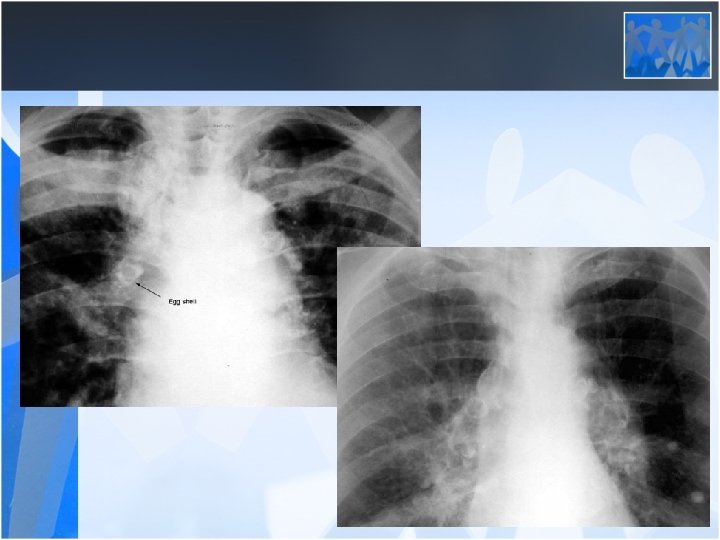

• Radiology is the most important diagnostic method for silicosis • Mainly upper and middle zone 3 -10 mm noduler opacities (silicotic nodules) • ILO clasification p, q, r • Hiler calcification (Egg shell calcification) PMF: • Coalescence of radiologic opacities (conglomeration • Nodules>10 mm • ILO clasification A, B, C • Honey combing can be seen in end stage disease

• CWP does not progress after the worker has ceased mining (cessation of exposure) • Mixed dust pneumoconiosis can be seen in miners (together with silicosis) • Caplans Syndrome: Multipl pulmonary nodules+ Rheumatoid artritis in a coal miner • There is no specific treatment for pneumoconiosis – Early diagnosis – Cessation of exposure – Supportive treatment